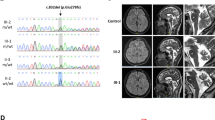

A 34-year-old man from non-consanguineous German parents without family history of ataxia or dementia presented with progressive upper limb hyperkinetic movements starting at age 30 years, subtle and slowly progressive gait disturbance starting at age 33 years, and impaired fine motor skills starting age 34 years. Childhood development had been normal and after finishing high school, he had worked as a medical technician. Upon neurological examination, the patient showed—apart from cerebellar oculomotor disturbances (saccadic smooth pursuit eye movements, hypermetric saccades), truncal (ataxic stance and gait) and appendicular ataxia (limb dysmetria, kinetic tremor)—myoclonic jerks of the upper limbs, and spastic gait disturbance. Chorea, dystonia, parkinsonism, epilepsy, and urinary tract symptoms were absent. Clinical signs of neuropathy were not present, and secondary sexual characteristics were normal. In the consecutive 3 years from first examination, gait and stance became more unstable and upper limb ataxia worsened, as reflected by an increase of 2.5 points on the Scale for the Assessment and Rating of Ataxia (SARA: 15to 17.5 points) [15]. Neuropsychological evaluation including the Test battery for attentional performance (TAP), the Wechsler Memory Scale-Revised (WMS-R) and the Verbal learning and memory test (VLMT) indicated pronounced attention deficits and a decline in memory performance (age and education adjusted scores were lower or far below average). Visuospatial dysfunction, affective and behavioural symptoms were not observed, thus not meeting the full characteristics of the cerebellar cognitive affective syndrome [16], as described for other previous STUB1 patients [4, 6,7,8]. Due to cognitive decline and worsening ataxia, he had to change his workplace within the company and to reduce the workload to part-time. Prolongation of the central motor conduction time to the lower limbs provided corroborative electrophysiological evidence for pyramidal tract damage. Nerve conduction studies revealed—clinically inapparent—axonal motor neuropathy. In addition to severe cerebellar atrophy, MRI brain scan showed T2-weighted hyperintensity in the dentate nuclei and bilateral parietal atrophy (Fig. 1). Whole-exome sequencing of the index patient revealed a previously unreported heterozygous start-lost loss-of-function (LoF) variant c.3G>A in the start codon of STUB1 (NM_005861.4: p.?). This variant is absent in both 13,140 in-house WES/WGS datasets as well as in the 276,000 alleles of gnomAD. Not only all exonic, but also all intronic regions were covered with a coverage of > 20× (except merely a 56 base pair region in intron 1, which was still covered with > 13×) by whole exome sequencing, making it unlikely that a putative second variant in the intronic region of STUB1 (and thus a possible autosomal-recessive mode of inheritance) would have been missed (Fig. 2a). Likewise, WES-based CNV analysis by ClinCNV (https://www.biorxiv.org/content/10.1101/837971v1) did not reveal any CNVs within the chromosomal region 16p13.3. Together with the identification of two SNPs in neighbouring RHBDL1 in a heterozygous state (rs111852492 and rs370469600, located 3369 and 2851 bp upstream of the STUB1 transcript, respectively), these analyses did not provide any evidence that a putative CNV (e.g., a microdeletion) would have been missed. Sanger sequencing confirmed presence of the variant in the index patient, and its absence in the other family members including both parents (Fig. 2b, c), with paternity confirmed by analysis of five short-tandem-repeat (STR) loci in the index patients and both parents, thus demonstrating de novo occurrence of this variant. The absence of the variant not only in the parents, but also in both siblings (Fig. 2b) not only corroborates potential pathogenicity of the variant, but also makes it less likely that a putative mosaicism in the parents might have been overlooked.

Genetic findings of the index patient and his family. a WES of the index patient shows that all exonic (E1–E7) and intronic regions (I1–I6) were covered with a coverage of ≥ 20× (except a 56 bp region in intron 1, which was however, also still covered with ≥ 13×, indicated in light green). The heterozygous c.3G > A STUB1 variant in the initiation codon is indicated with a black arrow. b Pedigree tree and c electropherograms demonstrating de novo occurrence of the heterozygous c.3G>A STUB1 variant (= M) in the index patient. This mutation was absent in both unaffected parents and siblings. The filled symbol represents the affected patient, and open symbols asymptomatic family members. The index patient is marked with an arrow

The c.3G>A variant was predicted in silico to cause a start-lost effect on protein translation. In line with this prediction, STUB1 protein expression in PBMCs was markedly decreased in the mutation carrier (reduced to ~ 30% compared to his parents; Fig. 3a, b). Specificity of the antibody to detect STUB1 was demonstrated by use of cell lysates of STUB1 iPSC-derived neuronal cells where a strong band was visible at the predicted molecular weight of 35 kDa for STUB1 wild-type, but not STUB1 knock-out cells, serving as positive and negative controls, respectively, for the Western Blot analyses. In sum, these protein analyses suggest loss-of-function (LoF) as the underlying disease mechanism of this STUB1 variant.

STUB1 protein and mRNA expression in PBMCs, and phenotypic spectrum of de novo STUB1-disease in the index patient. mRNA and proteins were extracted from PBMCs of the index patient (II.1) and his parents (I.1 and I.2). a Levels of STUB1 protein were quantified using Western Blot analysis, and were markedly reduced in the index patient (II.1) compared to both parents (I.1 and I.2). Equal protein loading is demonstrated using anti-β-actin monoclonal antibodies. Specificity of the antibodies was demonstrated using cell lysates from iPSC-derived neurons. A strong band was visible at the predicted molecular weight of 35 kDa for STUB1 wilde-type (iN WT), but not STUB1 knock-out cells (iN KO). b Densitometric analysis of three independent experiments shows decreased STUB1 expression in the index patient relative to β-actin. c Expression of STUB1 mRNA was measured using qRT-PCR (in three independent experiments), and was similar in the index patient and his parents, and two unrelated controls (C-1 and C-2). Differences in means for b and c were assessed with ANOVA followed by Tukey’s post-hoc test. Means and standard deviations are shown. n.s., non-significant (p > 0.05), *p < 0.05, **p < 0.01. d The phenotypic spectrum of the index patient with de novo STUB1-disease consists of ataxia, pyramidal tract damage, hyperkinetic movement disorder, and cognitive decline as part of the multisystemic disease spectrum in STUB1-disease

As predicted for a start-lost variant that only affects protein translation, not transcription, mRNA levels encoded by STUB1 were unchanged in PBMCs (Fig. 3c). Both STUB1 protein expression and mRNA levels were normal in the parents (Fig. 3a–c), adding further evidence that no putative mosaicism or second, inherited STUB1 variant (e.g., intronic or CNV) in the family has been missed.